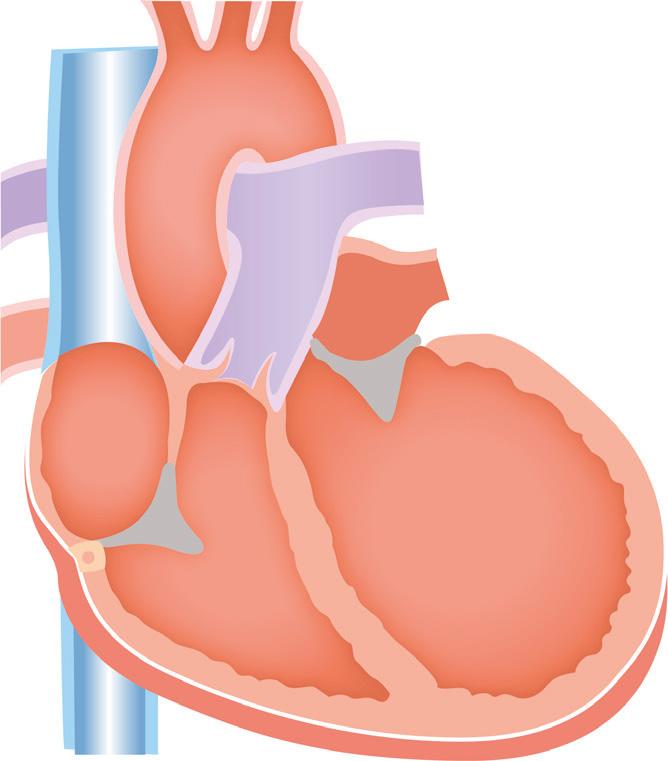

Tenemos el score de Killip que establece una clasificación clínica radiológica al ingreso del paciente con SCACEST.

También contamos con el score de Forrester, que correlaciona datos hemodinámicos, como índice cardíaco (IC) y presión capilar pulmonar (PCP), así como datos clínicos en los pacientes que sufren una insuficiencia cardiaca tras un infarto de miocardio (IC normal es > 2.2 L/minuto/m 2 y PCP normal < 18 mmHg).

Clase Hallazgos clínicos Mortalidad I Sin signos ni síntomas de 0 a 5%

estertores o crepitantes, 3er ruido o aumento de PV

10 a 20%

Edema pulmonar 35 a 45%

Shock cardiogénico: hipotensión y vasoconstricción periférica

85 a 95%